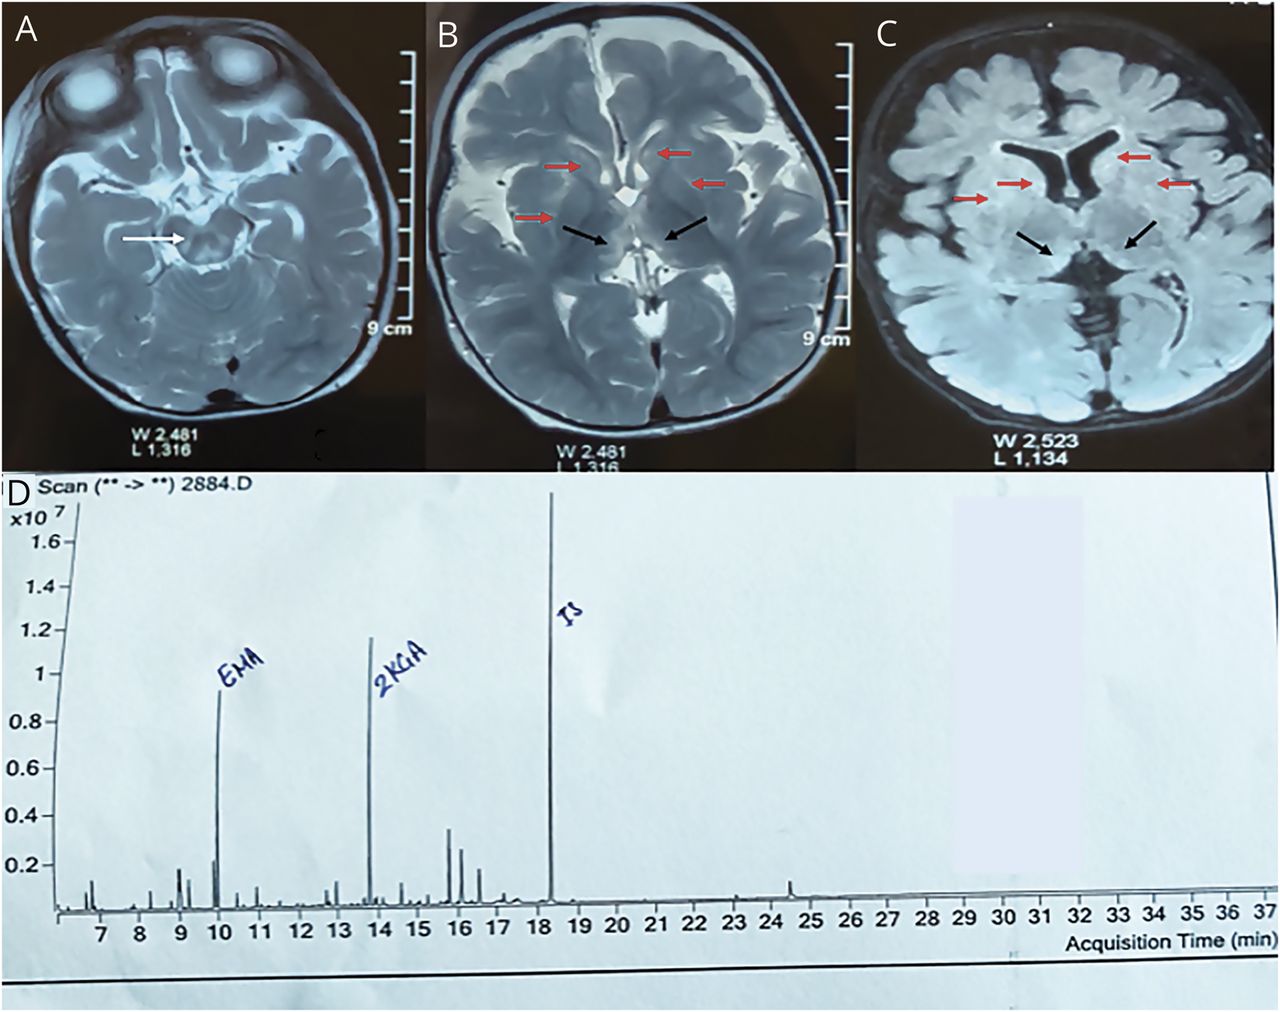

T2加权(A, B)和T2 fluid-attenuated反转恢复(C)轴向图像显示hyperintensities在中脑被盖;白色箭头),双边尾状核、壳核(红色箭头)和丘脑枕区(黑色箭头)。Total ion chromatogram (D) of urine metabolites by GCMS shows increased excretion of ethylmalonic acid (EMA), 2-ketoglutaric acid (2-KGA), isobutrylglycine, and isovalerylglycine.